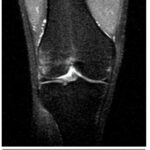

Valgo

Dibujo que representa un traumatismo directo sobre la cara lateral de la rodilla.

Imagen coronal de secuencia potenciada en T2 con saturación grasa de la rodilla derecha en paciente con lesión por traumatismo en valgo. Edema óseo en la

Fuente: https://epos.myesr.org/posterimage/esr/seram2014/124014/mediagallery/577012

Patrones de lesión de rodilla | Caso de radiología | Radiopaedia.org

Valgo puro

La lesión por una fuerza en valgo se presenta por lo general sobre una articulación levemente flexionada, originando un desplazamiento medial de la tibia y los cóndilos femorales, con distracciones severas en las estructuras de soporte medial de la articulación.

Patrones de edema óseo:

- Contusiones en la vertiente lateral de la tibia y/o vertiente lateral de cóndilos femorales por impacto.

Lesiones de partes blandas:

- Desgarro del ligamento colateral medial.

- Rotura del ligamento cruzado anterior o posterior, dependiendo del grado de fuerza aplicada, y su predominancia sobre la tibia o fémur, respectivamente.

El traumatismo de la rodilla en valgo, asociado a flexión y rotación externa de la tibia, es considerado como el tipo de presentación más frecuente dentro de las lesiones en valgo. Incluso se ha descrito como el mecanismo traumático más común de las lesiones complejas de rodilla, representando alrededor del 46%.

Este tipo de lesiones se presentan de manera usual en situaciones de rápida desaceleración o cambios súbitos de dirección, por lo que comúnmente se observa en jugadores de fútbol o esquiadores, entre otros. Este tipo de maniobras origina una sobrecarga sobre el ligamento cruzado anterior, que puede dar como resultado su rotura; como consecuencia, se produce una subluxación anterolateral de la tibia, y luego, una impactación del cóndilo femoral lateral con la vertiente posterolateral del platillo tibial. De esta situación podemos encontrar los siguientes hallazgos:[xxv]

- Contusiones en la porción media y/o posterior del cóndilo femoral externo y esquina tibial posterolateral por impactación.

- Contusiones en el cóndilo femoral interno y esquina tibial posteromedial por contragolpe, tras la resolución de la fuerza en valgo.

- Rotura del ligamento colateral medial y ligamento cruzado anterior.

- Mayor riesgo de lesión del menisco interno o externo. De manera ocasional, desgarro de la cápsula posterior y ligamento arcuato/poplíteo.

Ante la presencia de este patrón de edema óseo, es importante valorar la integridad del LCA, teniendo en cuenta que, por su localización y trayecto desde el cóndilo femoral lateral en la escotadura intercondílea hasta su inserción distal en la espina tibial anterior, se visualiza mejor en un plano sagital oblicuo, pero nunca olvidar que se debe valorar también en los planos axial y coronal.[xxvi]